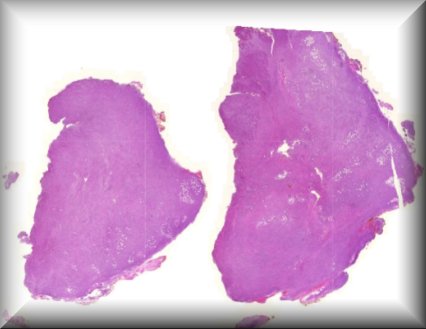

Susan Kennedy: Exenteration specimen of a 70-year-old female who underwent multiple (14) surgeries for conjunctival melanoma over a period of two years. |